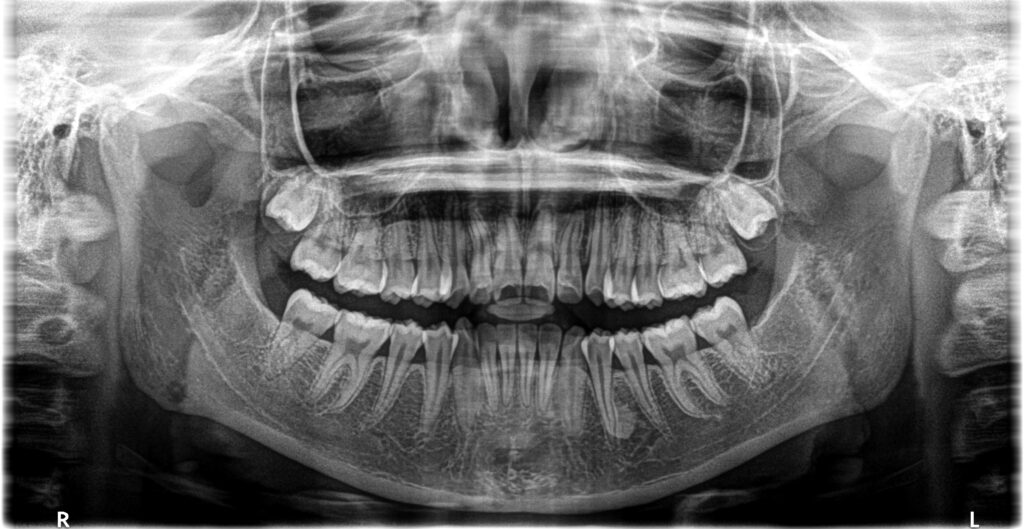

- 初診:2016年、9歳女児

- 主訴:出っ歯と歯の隙間がきになる。

- 診断:2級過蓋咬合、上下永久歯(犬歯)萌出スペース不足

- 治療方針:非抜歯で行う。虫歯予防(フッ素)、歯磨き指導、上下拡大床→咬合関係改善のツインブロック(2級→1級関係へ)→マウスピース矯正→下親知らずの抜歯、保定→メンテナンス

13歳頃、永久歯列になったところで、1期治療終了。虫歯のコントロール、歯磨き指導も十分に行ったため、虫歯や歯肉炎の発生もなく理想的な状態で完了できたと思います。あとは、高校1~2年生くらいに下顎の埋伏親知らずを抜歯して、通えれば20歳くらいまで半年メンテナンスが良いかもしれません。本当に口腔内の良好維持を考えている歯科医は、矯正で一時的に治った状態に満足しません。後戻りも考慮して、適齢期の親知らずの抜歯を行ったり、習癖の改善に取り組むでしょう。さらに患者さんが通院可能であれば、予後も追い続ける傾向があるでしょう。

下顎前歯叢生予防のため、高校1年になり、左右下埋伏の親知らずの抜歯を行いました。本人歯並びが良くなって、ホワイトニングも希望されましたので、行うことになりました。かなり白くなりました。個人的にこれが本当の人工物に頼らない理想的な治療方法(矯正+ホワイトニング)だと思ってます。これをもって、私の治療責任は果たされ、治療終了となります。恐らくこの子は、今のままの予防概念であれば、今後歯のトラブルに遭遇する確率は低いと考えられます。